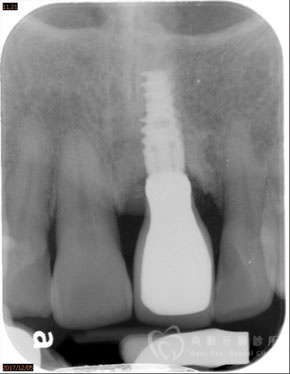

植牙案例四

植牙案例